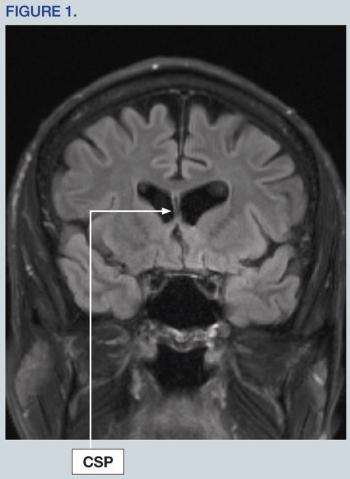

This article broadly reviews the pathophysiology of the most common forms of autoimmune encephalitis and provides guidelines tailored toward mental health professionals to best identify and manage these rare but important causes of neuropsychiatric illness.